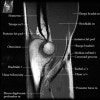

팔꿈치 관절의 MRI 단면 영상

4. MR Arthrography : Useful for evaluation of the collateral ligaments and cartilage surfaces.

5. Elbow Arthrography : UCL pathology in throwers, Osteochondral lesions and repair, Loose bodies